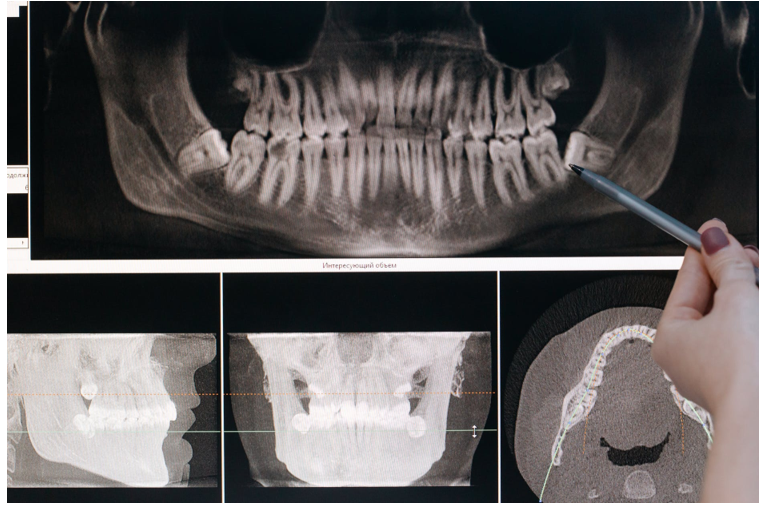

Перш ніж видаляти зуби, стоматолог запропонує зробити рентгенівські знімки. Тип рентгенівських знімків буде залежати від того, з якої причини вам показана ця процедура.

Для простого хворого зуба може бути достатньо звичайного рентгена зуба, який ви зазвичай отримуєте під час відвідування стоматолога раз на два роки. Однак для видалення зубів мудрості може знадобитися повний панорамний рентген, щоб стоматолог бачив всю внутрішню структуру зубів та ясен, які можуть постраждати.

Перед початком видалення стоматолог зробить рентгенівський знімок зуба. Це зображення допоможе оцінити кривизну та кут кореня зуба.